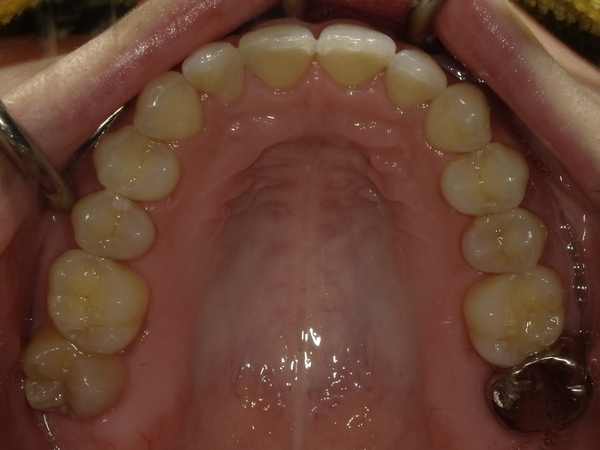

ガタガタとした歯並びや八重歯(叢生)CASE66